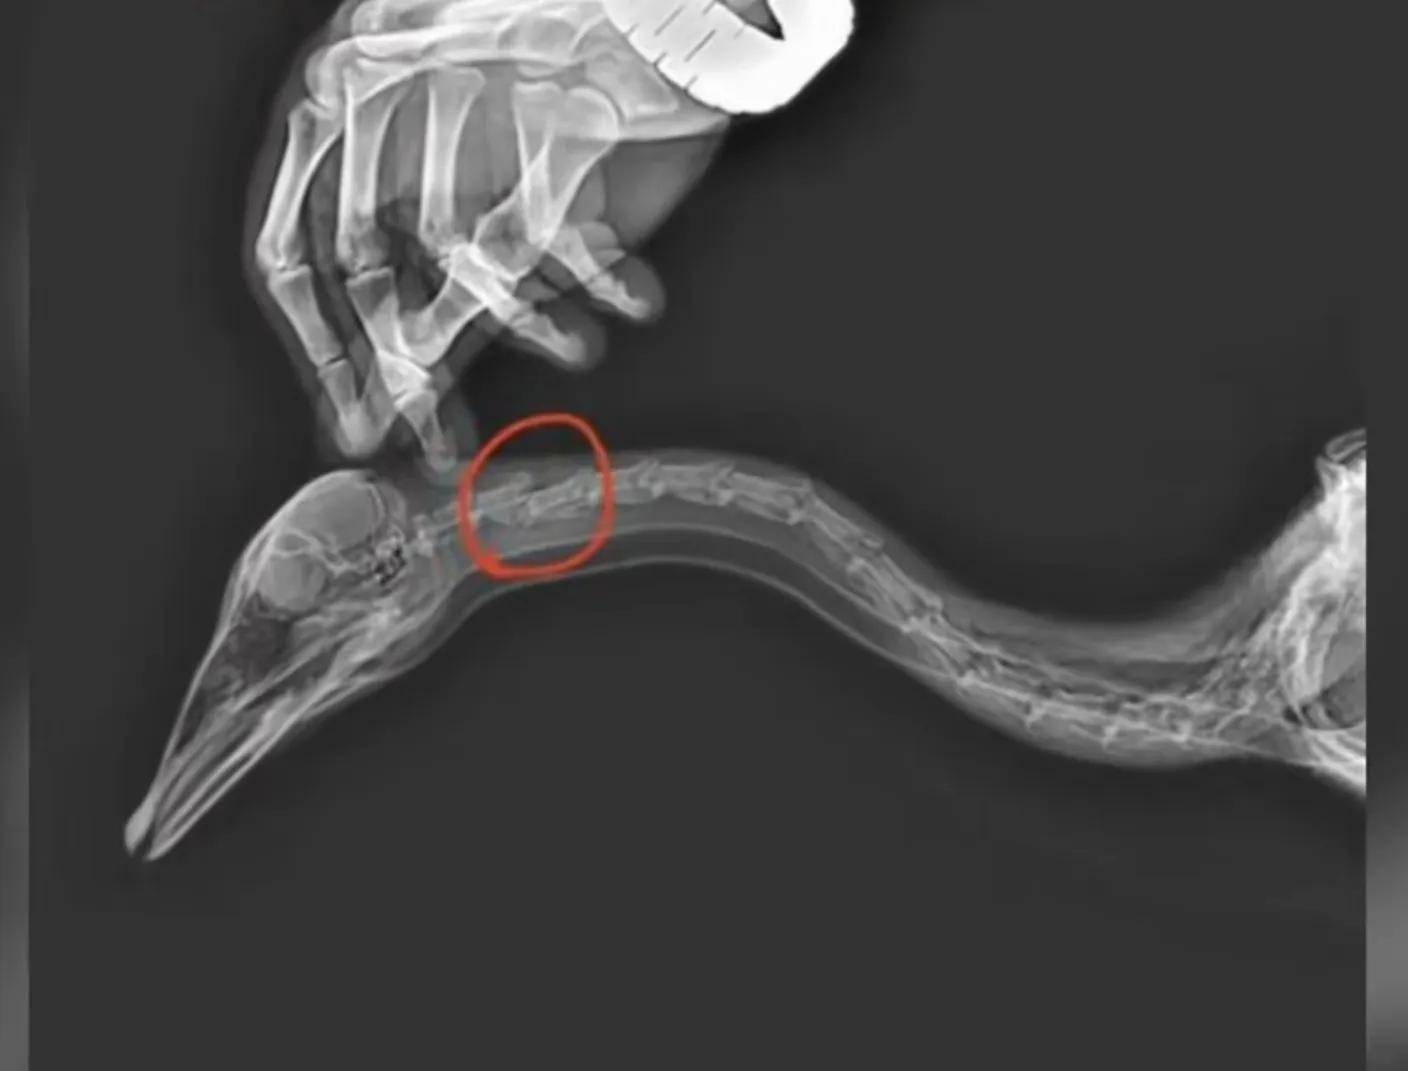

据介绍,斑头雁是公园里的网红鸟类,经常吸引游客观赏、拍照。但在最近的一次旅游游览中,一名游客踢了大雁的脖子,导致第二颈椎骨折,最终死亡。这一事件引发了公众的愤怒和谴责,许多人认为这是对自然缺乏尊重和虐待动物的行为。